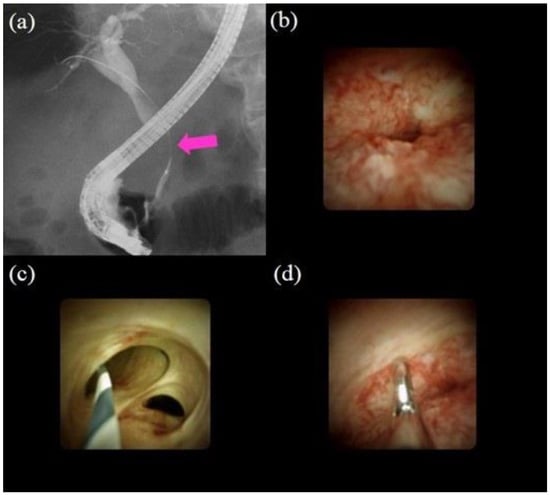

In a meta-analysis regarding POCS procedures, overall and serious adverse event rates of 7% and 1%, respectively, were reported [62]. When performing POCS, we must be mindful that cholangitis could be caused by an increase in intraductal pressure due to water irrigation during the procedure. Therefore, it is necessary to use antibiotic prophylaxis and perform biliary drainage to prevent cholangitis. Figure 3 highlights the procedure using POCS (SOC) to diagnose biliary strictures.

Figure 3.

Procedures of peroral cholangioscopy (POCS) and biopsy under direct view with POCS: (a) cholangiography showing the biliary stricture in the distal bile duct (pink arrow); (b) POCS showing an irregular papillogranular surface at the stricture, suggestive of malignancy; (c) POCS showing a fine network of thin vessels at the hilar bile duct, suggesting no malignancy; (d) forceps biopsy under direct view with POCS; the histological examination revealed adenocarcinoma.